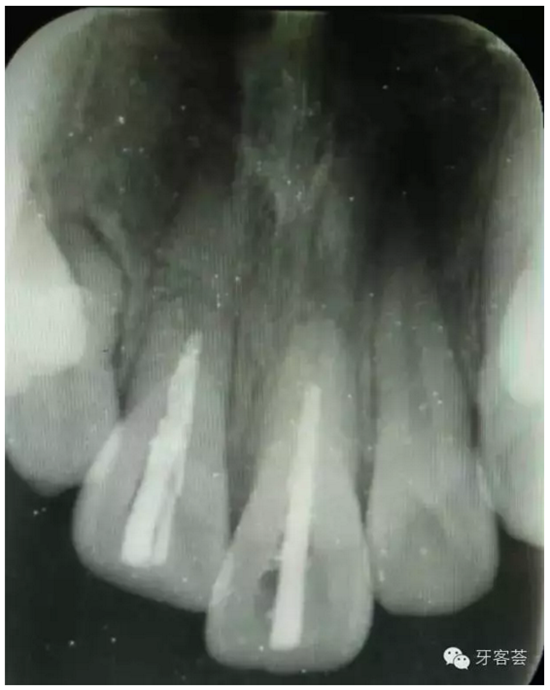

圖3:根尖片可以清晰看到11、21根尖橫折,這是根管治療過程中的試尖。